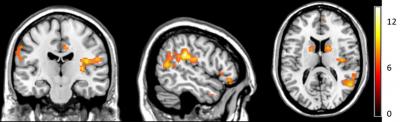

Researchers report that in three experiments involving 54 participants, significant distinctions emerged between self-touch and touch from others in neural processing at the cortical and spinal cord levels, with self-touch involving deactivation of several brain regions that were active during other-touch, as well as functional connectivity between the brain's sensorimotor cortex and insula and an elevated threshold for detection of additional tactile input.

Article #18-16278: "Distinction of self-produced touch and social touch at cortical and spinal cord levels," by Rebecca Böhme, Steven Hauser, Gregory Gerling, Markus Heilig, and Håkan Olausson.